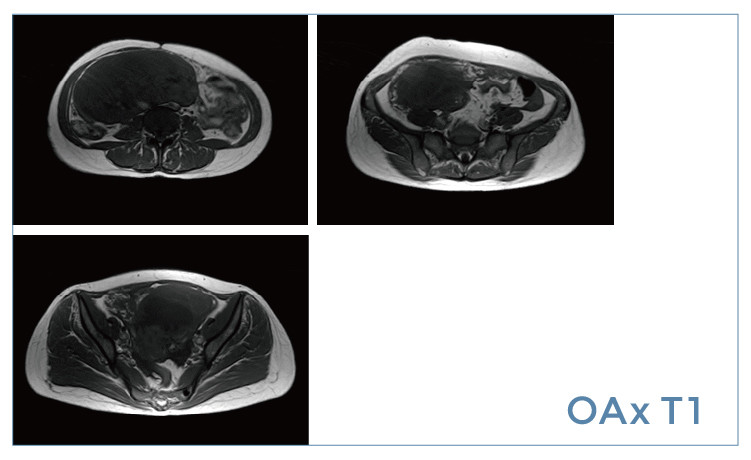

【朗润影像档案】20190419磁共振影像病例结果讨论